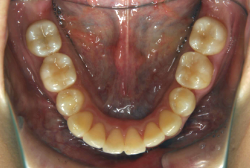

叢生(そうせい)

凸凹な歯並びのことを叢生といいます。矯正歯科に来院する患者様の主訴の中で、最も多いのが「配列の凸凹を真っ直ぐにしたい」というものです。歯の大きさと顎の大きさの調和がとれていないことが原因です。

凸凹を主体としたケースの場合、当院の平均治療期間は18ヶ月ですので、このケースは少し長めに経過しました。理由の一つは凸凹の程度がかなり重症だったと言うことですが、もう一つは、右下第2大臼歯が45度くらい前傾していたため、それを整直化させるために時間を要したと考えています。いずれにしても最終結果は大変よい状態と思います。

治療前は並びが乱れて見た目が悪いというのはもちろん問題ですが、歯科医学的に一番困るのは噛み合わせが悪いという点です。上下の犬歯(3番目の歯)は、上下的に離れた位置にあるため接触することができません。つまり歯としては存在していても、歯としては機能していないということです。